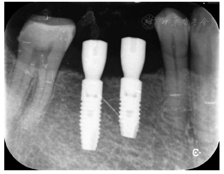

术后即刻拧入扫描杆,口内扫描数据导入DentalNavi软件,进行术后精度评价。结果显示45、46牙种植位置偏差均<0.3 mm,角度偏差<0.8°(图20)。

I期术后3个月复诊,患者自述种植区无明显不适,口内检查植体无明显松动,叩诊清音,牙龈愈合良好,X线检查种植体周围无明显阴影(图22),骨愈合良好。卸下愈合基台,穿龈形态良好,连接扫描杆进行口扫,氧化锆联冠修复,常规完成修复体制作与戴牙(图23)。